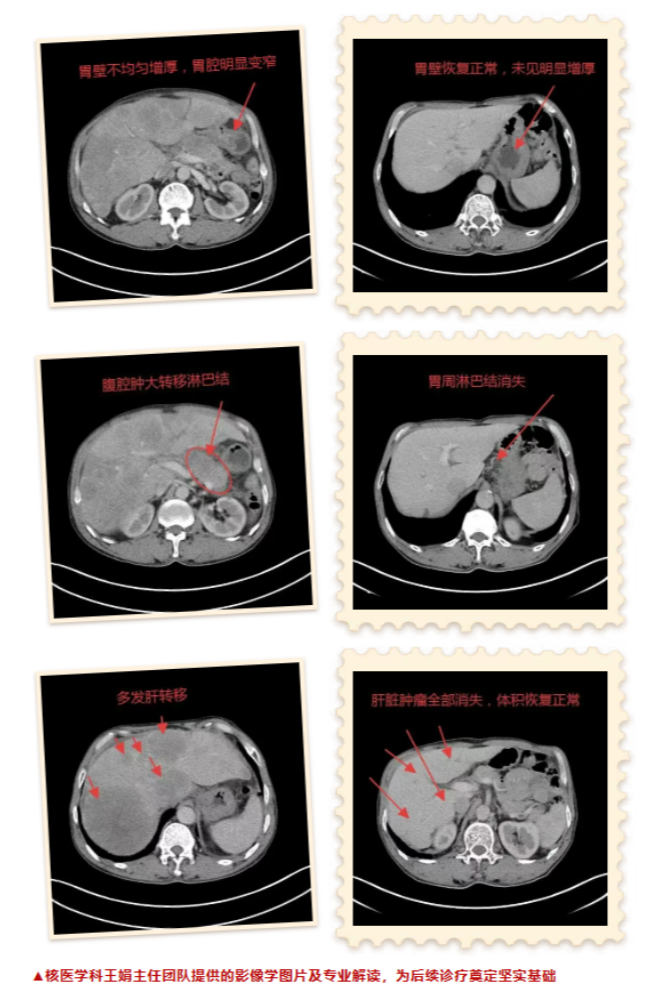

2020年10月,66歲的王先生因反復(fù)腹痛和消瘦前往晉城大醫(yī)院就診。完善CT檢查顯示:胃壁不均勻增厚,高度懷疑惡性病變;肝臟多發(fā)低密度影,提示轉(zhuǎn)移。病理明確診斷為:胃竇低分化腺癌。每一項檢查都在宣告著這場抗癌之戰(zhàn)的艱難。

時間見證奇跡。在醫(yī)護團隊的精心照護與王先生的積極配合下,近期王先生的復(fù)查結(jié)果讓所有人為之振奮:胃壁病灶和肝臟病灶全部消失,王先生的抗癌之路終于迎來了曙光!這不僅是醫(yī)學(xué)的勝利,更是生命的奇跡。